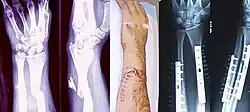

(a) closed fracture

(b) open fracture

(c) transverse fracture

(d) spiral fracture

(e) comminuted fracture

(f) impacted fracture

(g) greenstick fracture

(h) oblique fracture